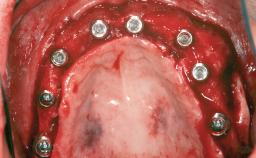

Ridge Preservation and Implant Placement for a Fixed Dental Prosthesis After a Car Accident

It is well known to clinicians that any removal of teeth will, over time, cause the dimensions of the alveolar ridge to be reduced by resorption of the bundle bone and by changes related to external modeling. This development is particularly evident in the crestal region with its thin buccal bone that consists of bundle bone almost entirely. The facial bone will rapidly resorb as blood supply from the periodontal ligament gets disrupted (Araújo and Lindhe 2005). There is no reason why traumatic tooth loss should not have the same consequences. It takes more than achieving implant osseointegration for a treatment outcome to be considered successful. No deficiency of bone or soft tissue is acceptable when an ideal esthetic outcome is the goal. Several articles (Sanz and coworkers 2011; Vignoletti and coworkers 2011) have reported on techniques of improving the alveolar ridge for implant treatment, notably focusing on protecting tissues from resorption.

Case Type Extended Space

Jaw Maxilla

Area Anterior|Posterior

# of Teeth 6

# of Implants 4

Type of Implants One-Piece|Reduced-Diameter